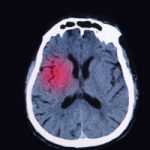

A TBI occurs when there is a blow, bump, or jolt to the head region, disrupting the normal function of the brain. TBIs can range in severity and not all head injuries result in a TBI. A mild version of a TBI is a concussion, which is a common occurrence.

Suffering a traumatic brain injury (TBI) increases the buildup of Alzheimer’s plaques in the brain, as found by a new study that suggests these plaques even form in areas not typical to Alzheimer’s disease.

Previous research has proposed that TBI can contribute to dementia, and this research was the premise the new study was based upon. The researchers found that moderate to severe TBI increased plaque buildup in nine middle-aged participants who were observed over a few months or years.

Participants with brain injuries and Alzheimer’s disease had plaque buildup in the posterior cingulate cortex, commonly seen in early Alzheimer’s. TBI participants also had plaque buildup in the cerebellum, which is responsible for motor control. Continue reading…